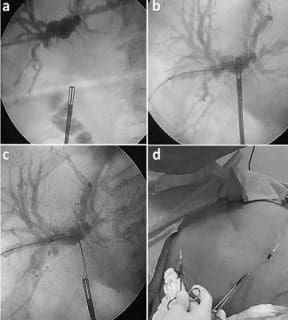

Posteriormente se exterioriza la guía, se fija el asa a la pared abdominal y se avanza el catéter trans-anastomótico (figura 2).

Figura 2. Secuencia del rendezvous percutáneo-laparoscópico: (a) avance de la pinza a través de la estenosis, (b) captura de la guía (c), exteriorización a través del puerto del flanco derecho y (d) colocación de un catéter trans-anastomótico en “U” (entrada y salida señaladas con las flechas) – Instrumentación Biliar Percutánea